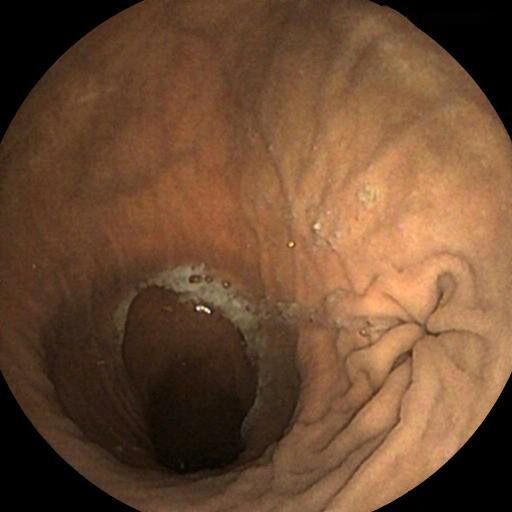

Typical Findings

Polyp Erosion Gastritis Ulcer